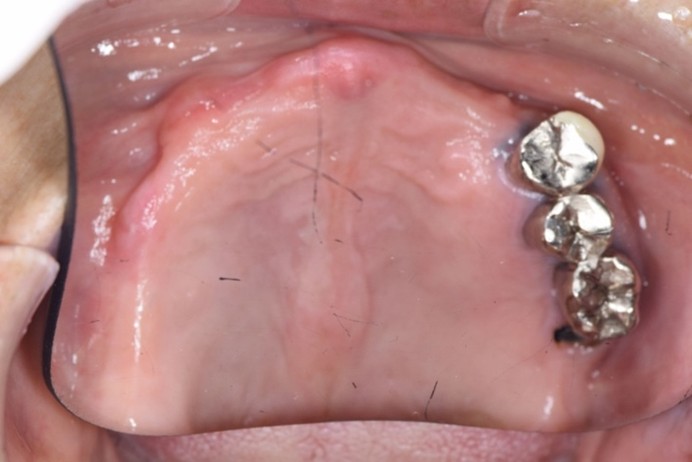

症例1

| 術前 | 術後 |

| ご来院時の主訴 | 入れ歯を入れたが落ちてくる。 インプラントの話を聞いたので入れ歯じゃなくてインプラントをしたい。 |

| 年代・性別 | 70代 女性 |

| 治療部位 | 上顎7〜7 |

| 治療費用 | 2,420,000円 |

| 手術回数 | 2回 |

| 治療期間 | 25か月 |

| 手術時間 | 90分×2回 |

| 治療回数 | 28回 |